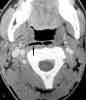

You order a CT scan of the orbits.Coronal (C) and axial (D) imagesconfirm the radiographic findingsof opacity of the ethmoid air cells(red arrows) and maxillary antrum(black arrow) caused by mucus andfluid. These images also define theextent of orbital edema and proptosis(yellow arrows).